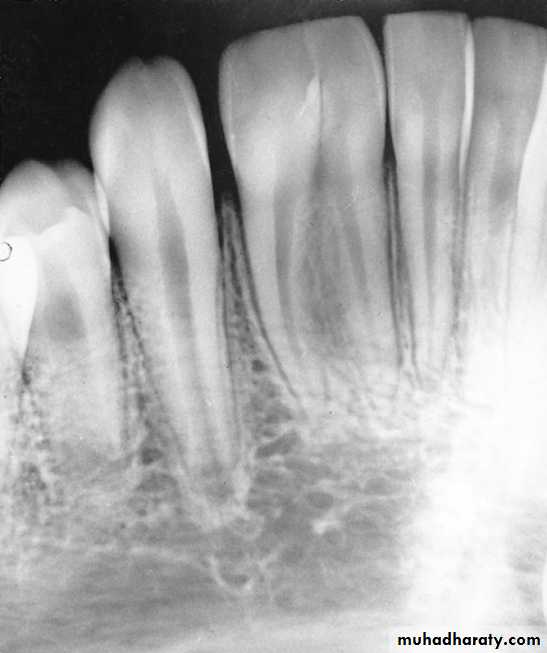

Deep caries in the first primary molar and due to that caries resorption in the bifurcation areaDeep caries in the mandibular second primary molar

Periapical radiographs